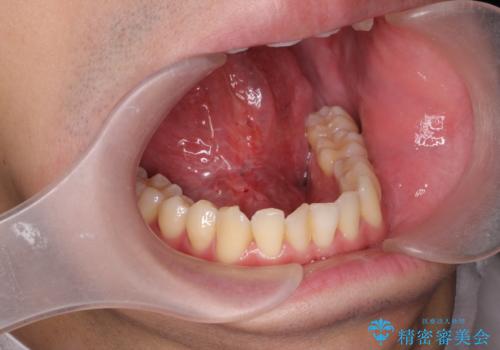

[ 舌小帯の形成 ] 滑舌を改善したい

担当医 大元洋佑

![[ 舌小帯の形成 ] 滑舌を改善したいの症例 治療前](https://seimitsushinbi.jp/wp/wp-content/uploads/2022/10/fa797540f242dace21c05a8161580df4-500x350.jpg?v=1665555891)

![[ 舌小帯の形成 ] 滑舌を改善したいの症例 治療後](https://seimitsushinbi.jp/wp/wp-content/uploads/2022/10/45c8c51b664db205e71949fb1e2ec432-500x350.jpg?v=1665555859)